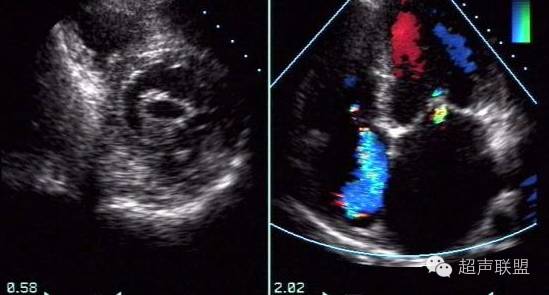

超声表现

M 型超声动图主要为二尖瓣运动曲线的改变。正常E 、A 双峰间的切迹消失,呈平台状(即“城墙样”改变)。后叶与前叶呈同向运动。

二维超声心动图中二尖瓣回声增强、增粗。尢其是瓣尖增厚,瓣膜开放受限,瓣口开放直径及面积均减小。

二维及M 型图中均可测得左房内径增大,有时测得右室或右室流出道径增宽。左室通常不增大。

二尖瓣狭窄左房附壁血栓♦ 二尖瓣活动能力减弱

脉冲多普勒超声心动图检查时,将取样容积置于左室流入道口或左房侧,见舒张期e 、a 两峰消失,频谱展宽呈宽带曲线。二尖瓣狭窄舒张期血流彩色多普勒于二尖瓣口左室侧可见彩色镶嵌样血流信号,流束变细,流速增快,血流颜色明亮而鲜艳。

二尖瓣狭窄并关闭不全♦ 合并关闭不全时收缩期在左房侧可见彩色镶嵌的二尖瓣口返流信号